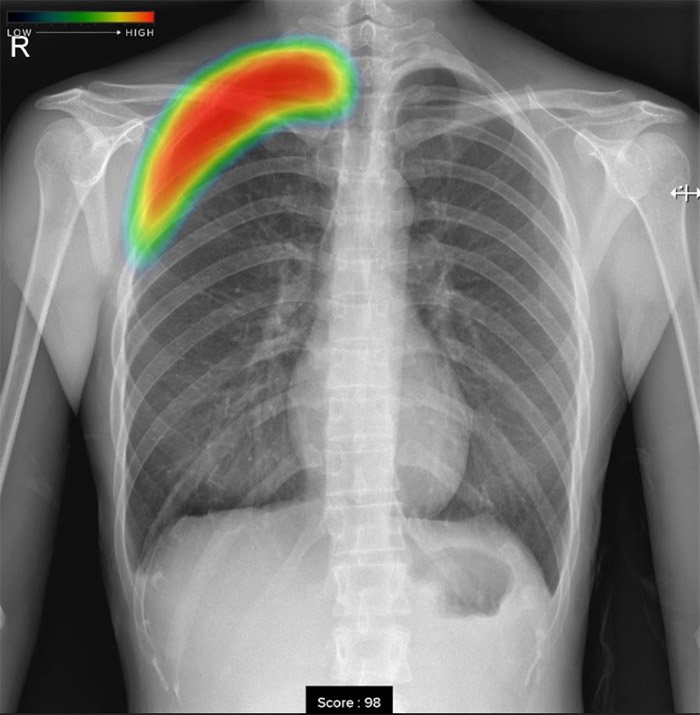

胸部レントゲン検査の場合、見る医師が少しでも異常がありそうと判断をしたら「要精査」とコメントし精密検査を行う流れになります。見落としがないように少しでも異常が疑われればやや過剰にでも異常と判断をいたします。そこでエルフ内科クリニックでは最新のAI技術を活用し、病変検出能が明らかに向上する「胸部X線画像病変検出ソフトウエアCXR-AID」を導入いたしました。

撮影画像を自動解析して、結節、腫瘤影、浸潤影、気胸が疑われる領域を検出しマーキングいたしますので、医師とAIがダブルチェックを行ない、診断精度を高めております。

• 気胸気胸